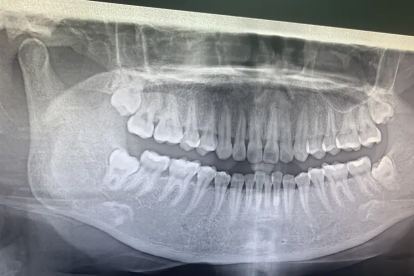

拔牙前需完善全景片或CT检查,评估牙根形态与邻牙关系。术后24小时内避免漱口和剧烈运动,72小时后可逐步恢复软食。出现持续出血、剧烈疼痛或发热应及时复诊。日常保持口腔清洁,使用氯己定含漱液辅助消炎,避免用患侧咀嚼直至拆线。